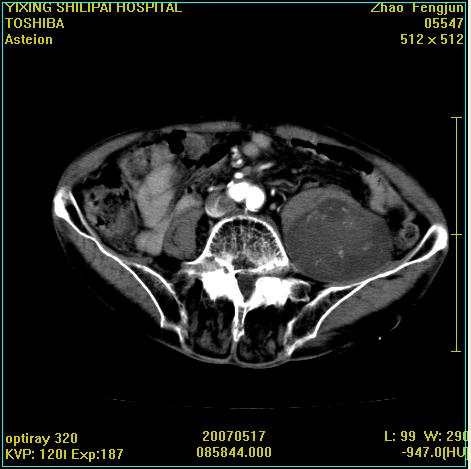

考虑:1、左侧腰大肌囊实性占位性病变(囊性神经根鞘瘤?);

2、右侧兰尾区囊性占位性病变(兰尾囊肿?囊腺癌?类癌?)

以下是引用xiaoniu在2007-5-26 10:45:00的发言:[br]腰大肌的病变应该没有问题,增强扫描还有轻度强化及细小血管影入内,应该排除脓肿,考虑占位性病变,腰大肌的占位多考虑:神经源性肿瘤。另外腹主动脉下端有真假腔的强化,考虑:主动脉夹层。[br][br][本贴已被 xiaoniu 于 2007-5-26 10:46:39 修改过]

以下是引用老爱克斯新网客在2007-5-26 18:26:00的发言:[br]1左下腹囊实性占位肿块,增强后不均匀强化,位于脊柱旁,椎体骨质无破坏软组织无肿胀,考虑神经源肿瘤神经鞘瘤可能大,2右下腹囊性占位性病变,增强后囊壁强化,考虑阑尾囊肿或囊腺瘤,